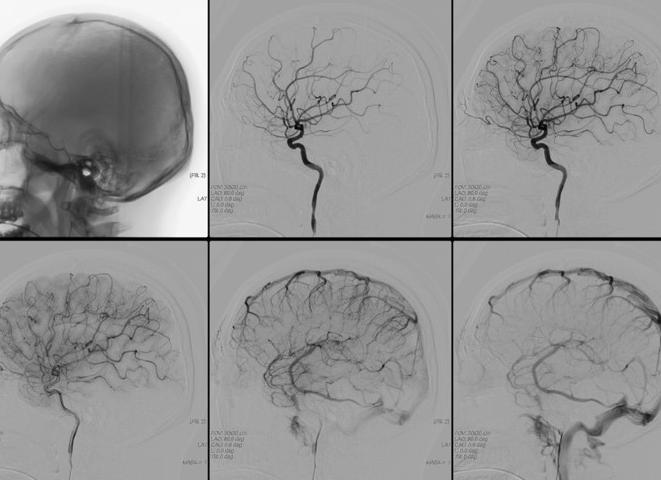

Церебральная ангиография сосудов головного мозга — это современная инструментальная диагностическая процедура, которая позволяет в буквальном смысле увидеть необходимый участок кровеносной системы. Перед тем как проводится сканирование, в исследуемый сосуд вводят контрастное вещество. С его помощью на рентгеновском снимке будут четко просматриваться все нарушения вен и артерий, если они есть. Подробнее ...

Ангиографический способ изучения на сегодня является лучшим методом диагностики сосудистых патологий. Он позволяет получить функциональную и анатомическую картину движения тока. Проводится под воздействием рентгеновских лучей или магнитного поля. Наиболее информативно с введением препаратов для создания контраста с другими тканями. Препарат вводят через катетер, установленный в позвоночную, сонную артерию или в бедерную. В этом случае говорят о катетеризационном методе. Если препарат вводят через прокол изучаемого сосуда, метод называют пункционным. Подробнее ...